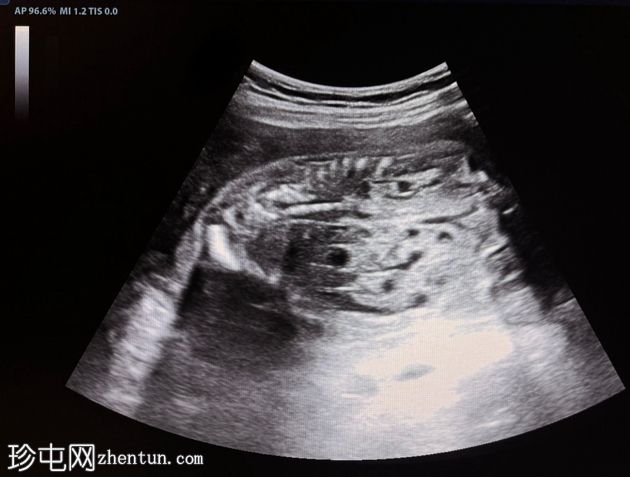

横切面

纵切面

胎儿双肾增大,回声增强,伴多发性小实质囊肿

羊水过少,羊水指数(AFI)= 3cm(未显示)

上述特征符合常染色体隐性多囊肾病的诊断。